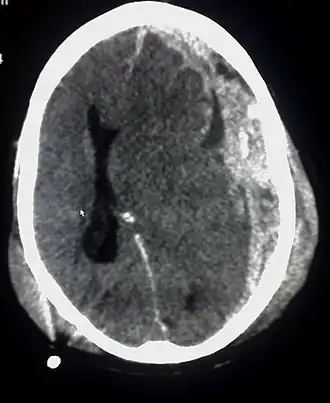

Hematoma subdural

Un hematoma subdural es una acumulación de sangre entre la duramadre que es la membrana que cubre el cerebro y la aracnoides, una de las capas de las meninges. Un hematoma así constituido se debe a la rotura traumática de vasos venosos que atraviesan el espacio subdural, por lo tanto se produce una separación entre las capas de la aracnoides y la duramadre. Los hematomas subdurales pueden causar un aumento de la presión intracraneal, compresión y daño del tejido cerebral. Un hematoma subdural agudo tiene una mortalidad elevada, por lo que se considera una urgencia médica,[1] es de alrededor de 60 a 80 %.[2]